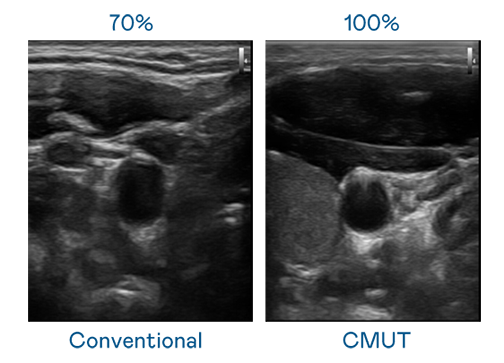

CMUT 技术是一种用电容式微机电元件来产生超音波讯号的技术。与传统 PZT 压电式技术相比,CMUT 频宽增加 30%,更宽频的超音波讯号让影像解析度大幅提升,是实现高影像品质医疗超音波扫描、促进精准医疗发展的关键技术。

超音波影像的解析度高低,首先取决于探头能发出的讯号频宽。人生就是搏 CMUT 可提供高清晰的超音波讯号,提供高频宽、高灵敏度、影像纹理细节更高的超音波影像,协助医护人员缩短影像判读时间及利用精准的医疗影像进行诊断。